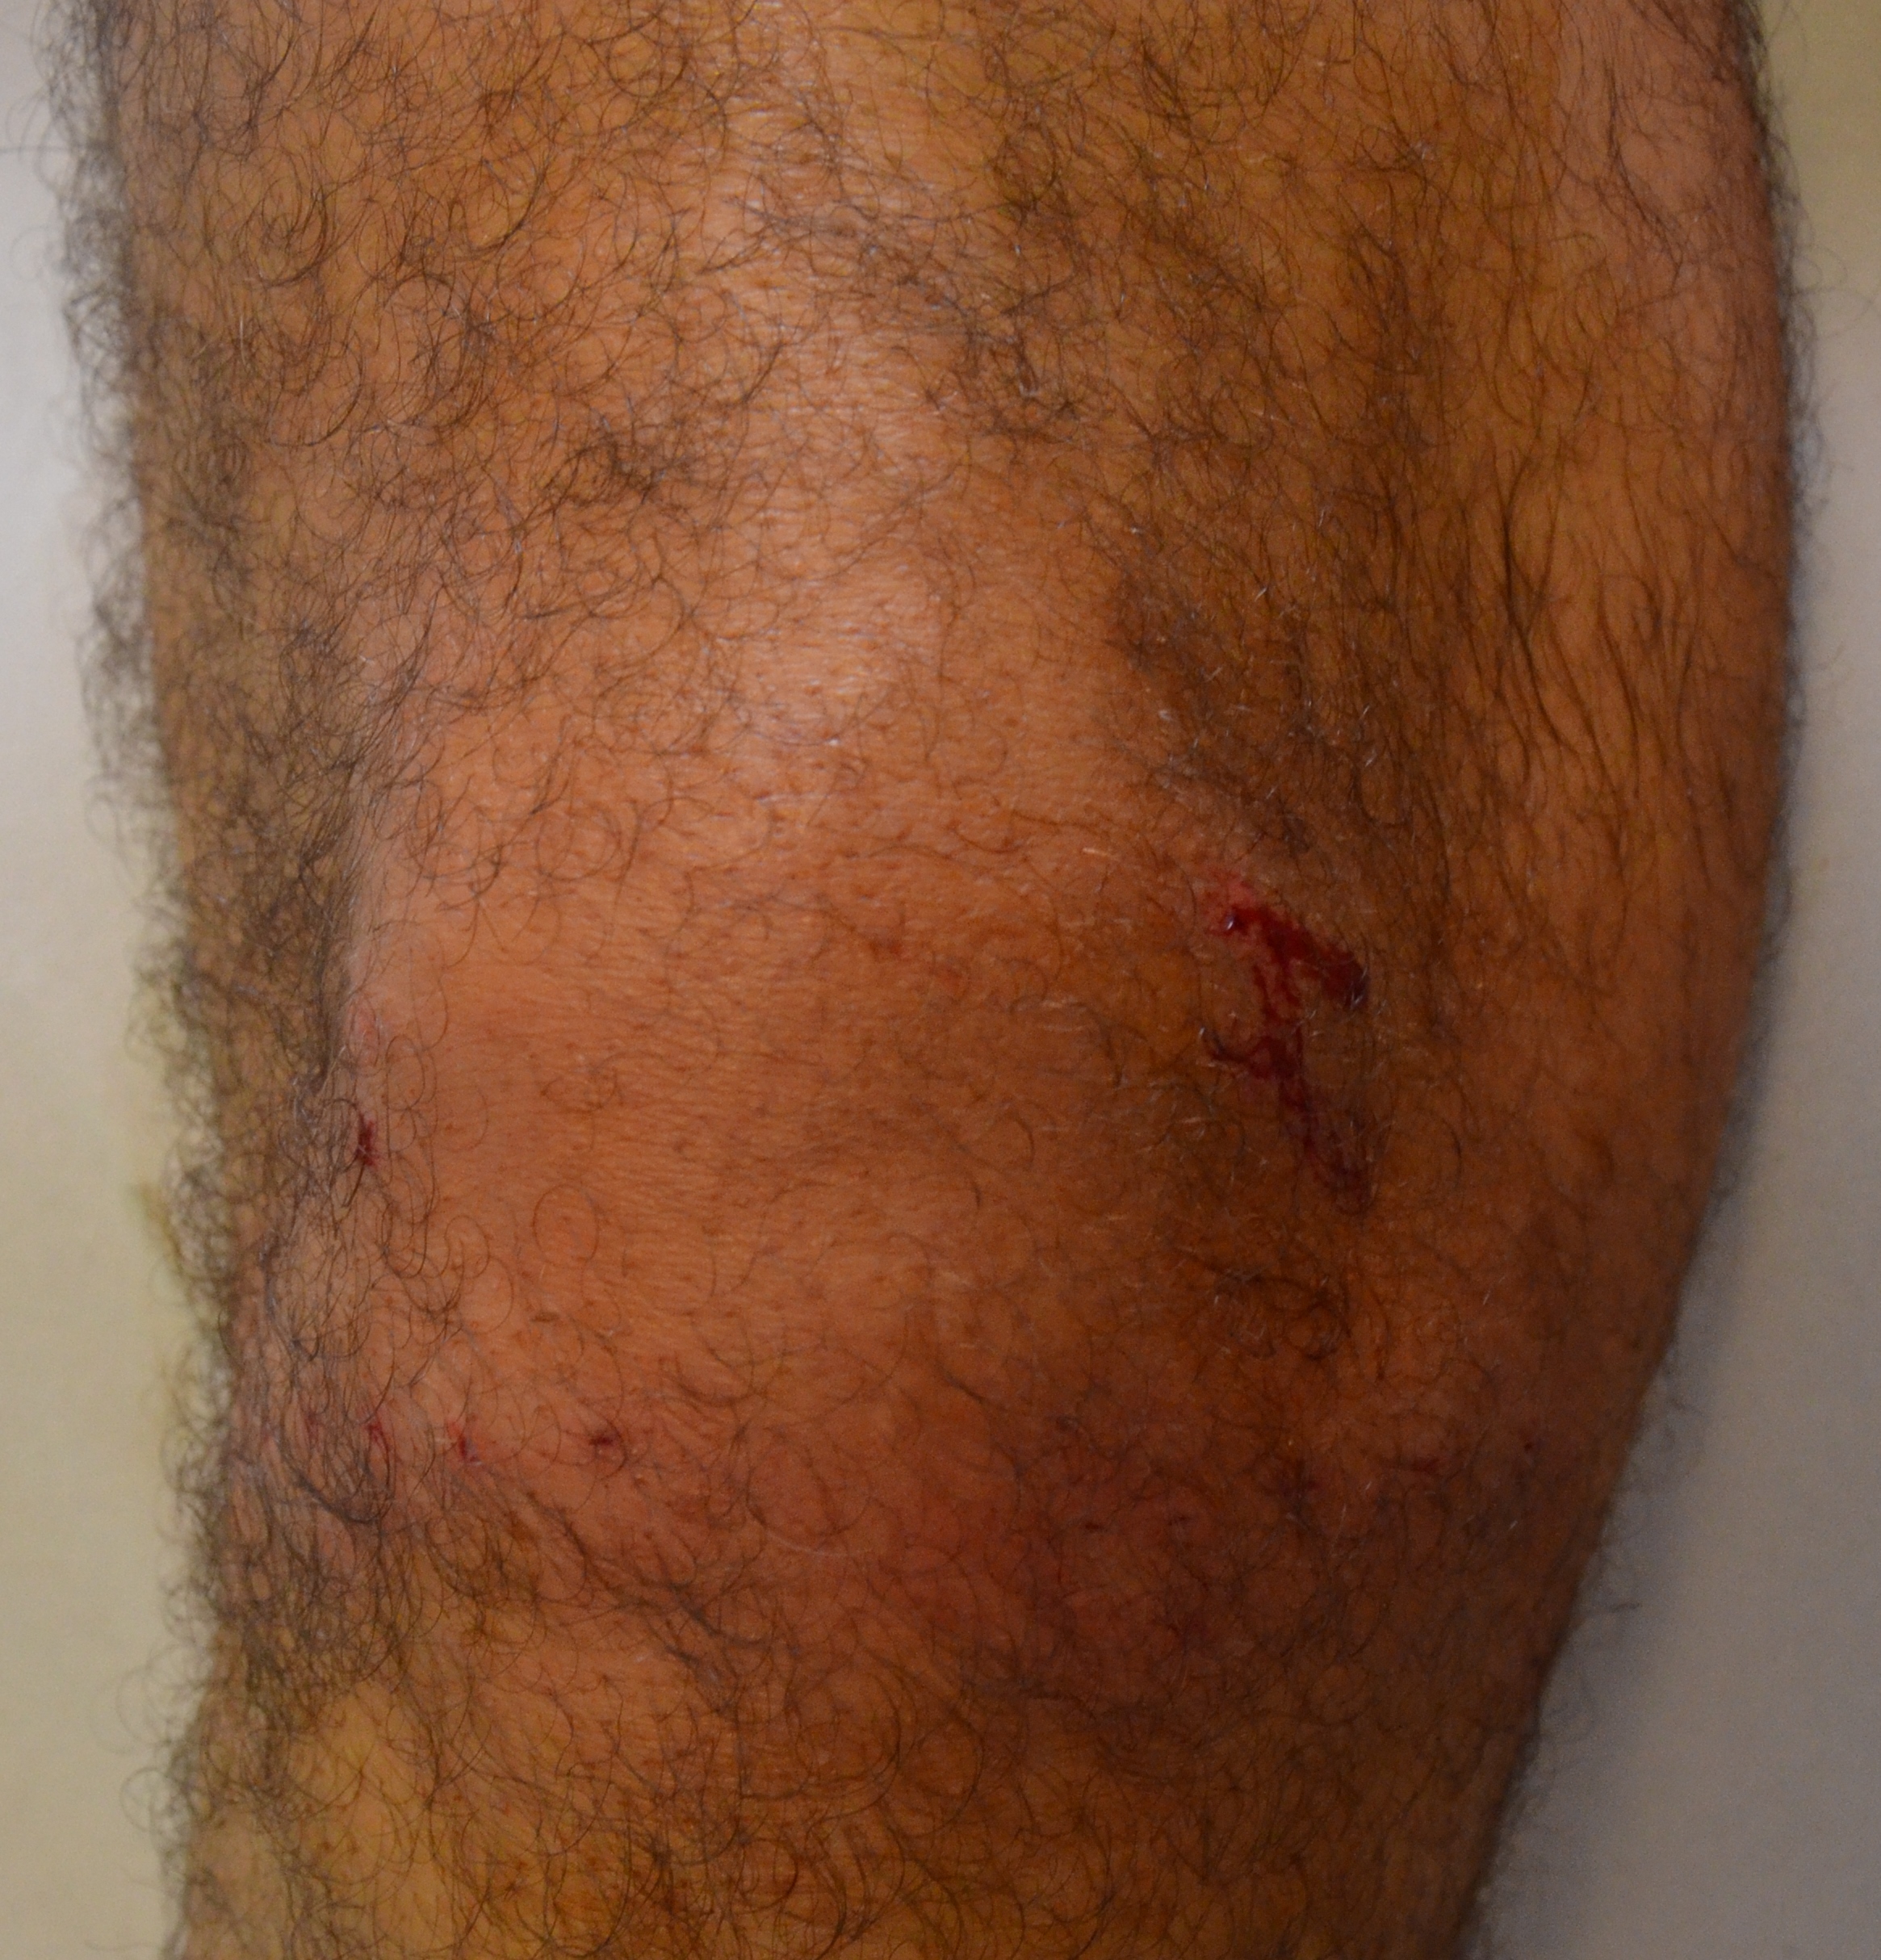

Los implantes de oro periarticulares pueden colocarse tanto en artrosis primaria como secundaria. En este caso se colocaron en una gonartrosis secundaria a fractura por accidente de moto. El resultado postoperatorio inmediato ha sido excelente, y luego de tres semanas de la intervención, el paciente refiere una recuperación sintomática importante, con ausencia de claudicación de la marcha y progresiva ganancia de la movilidad articular. Es manifiesto el grado de satisfacción por parte del paciente.

En las imágenes pueden observarse la Rx, el momento de la colocación de un implante, y el postoperatorio inmediato tras la colocación de los implantes de oro.